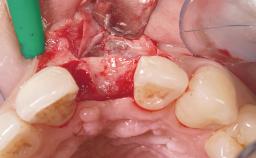

Early Placement of an Implant in a Maxillary Right Central Incisor Site

Bone Augmentation | Horizontal|Simultaneous |

Augmentation Materials | Autogenous chips|Xenogenous|Membrane |